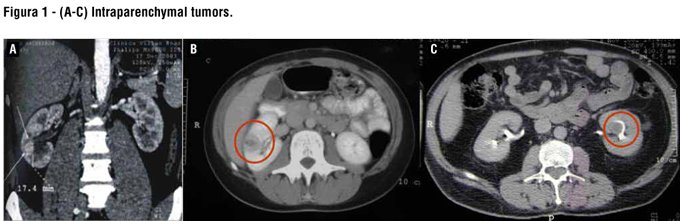

However, renal occult tumors diagnosed by imaging techniques represent greater technical difficulties for localization and resection, and may increase the chances of complications (8) (Figures 1A-C). To precisely locate the tumor during surgical resection, intraoperative ultrasound during the operation has been used successfully (9).

The authors performed a retrospective analysis of patients undergoing partial nephrectomy at their institution and all subjects with endophytic tumors treated with anatrophic nephrotomy were identified (Figures 2A-D). Patient demographics, perioperative, functional and oncologic results were evaluated. Among 554 renal tumors treated between 06/2006 and 06/2010, in 187 it was performed partial nephrectomy, and ten patients underwent partial nephrectomy through anatrophic nephrotomy.